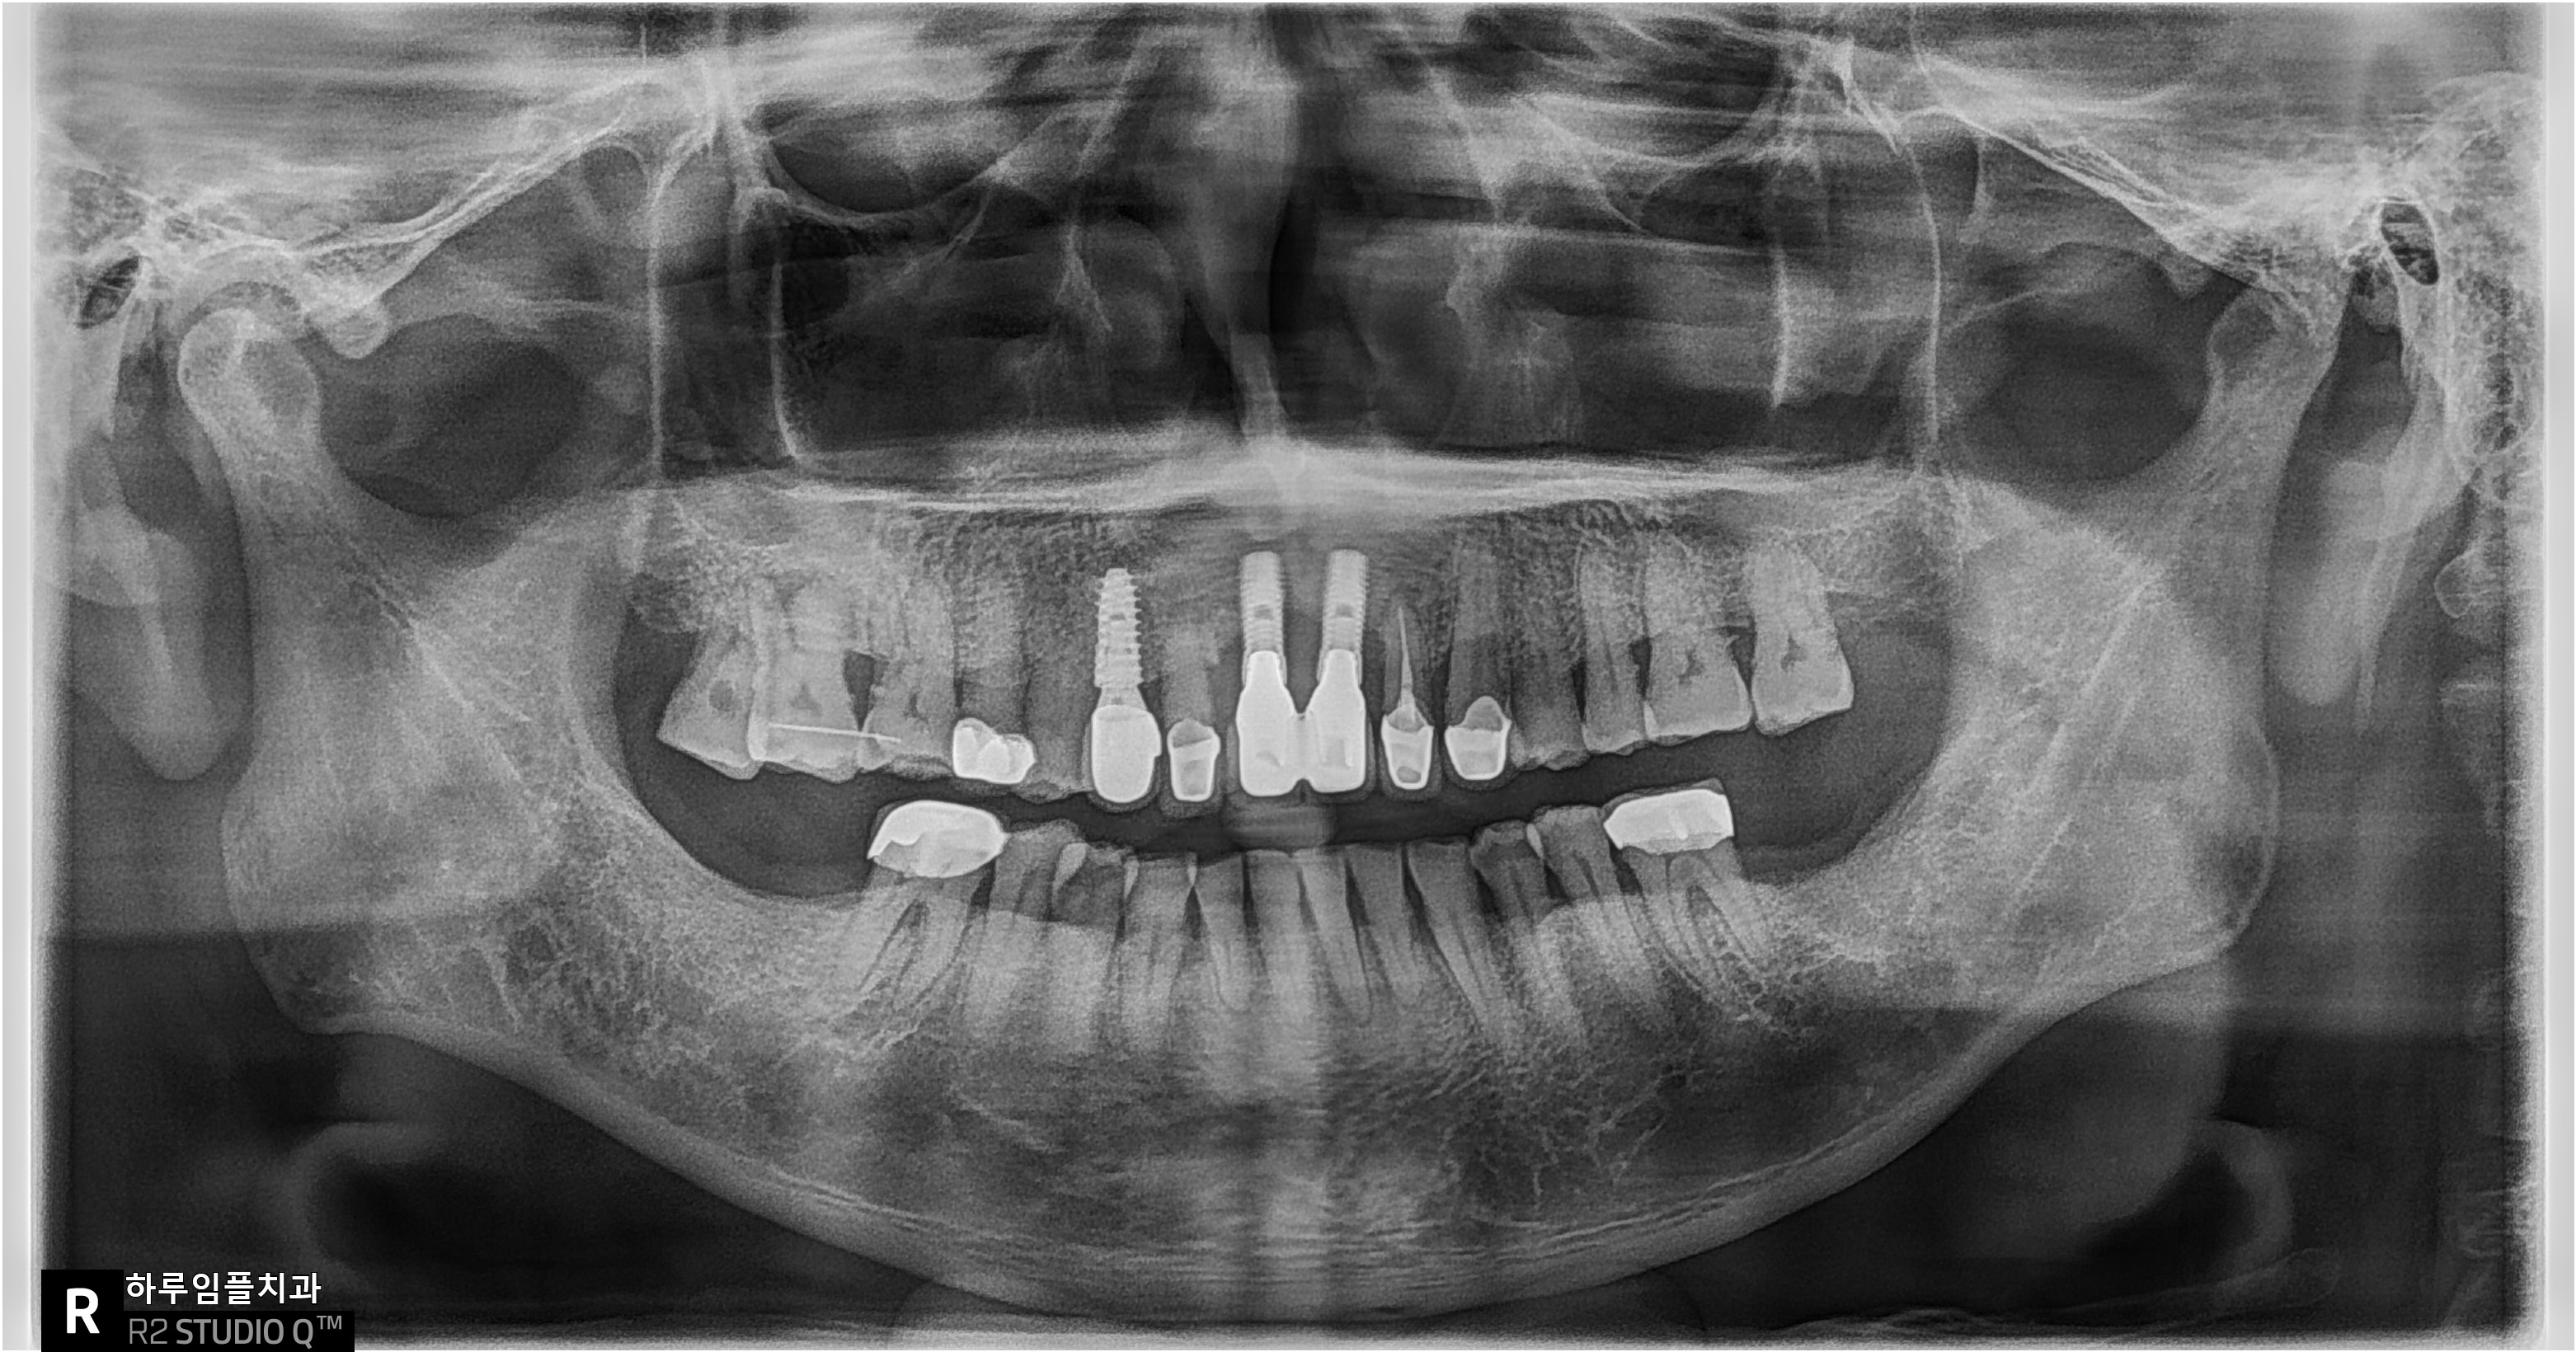

방사선 사진에서는

픽스쳐 주변 뼈의 50% 이상이

이미 녹은 상태였습니다.

전치부는 뼈가 워낙 얇기 때문에,

일반 금속치근을 심으면

처음 몇 년은 괜찮아도 5~10년 사이에

결과가 급격히 나빠지는 경우가

매우 흔합니다.

뼈가 얇아 시간이 지나면 잇몸이 내려가고

나사선이 잇몸 밖으로 노출되면서

염증이 반복되고,

결국 뼈가 녹아내리는 구조죠.

실제로 환자분이 염증이 생긴 이유도

정확히 이 과정 때문입니다.